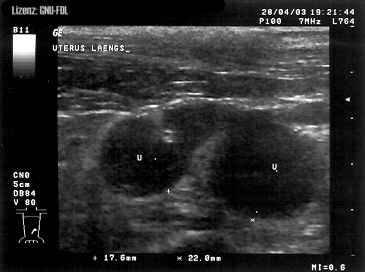

Pyometra (z řec. pyon, hnis, a metra, děloha) je zánět dělohy, při kterém dojde k naplnění děložní dutiny hnisavým výpotkem. U většiny savců včetně člověka vzniká pyometra rozvojem zánětu děložní sliznice, neboli endometritidy. Výjimkou je fena a kočka, kde hnisavý zánět dělohy vzniká na podkladě hormonálně podmíněných změn v děloze nekastrovaných a nenakrytých fen a koček po proběhlé říji. Wikipedie

Pyometra, neboli hnisavý zánět dělohy, se vyskytuje ve dvou formách- otevřená pyometra a pyometra uzavřená. Při otevřené formě se hnis, vytvářející se v děloze, dostává otevřenými porodními cestami ven.

Pyometra neboli hnisavý zánět dělohy je plíživě probíhající onemocnění a majitelé jej často zaznamenají až v rozvinutém stádiu. Představuje potenciálně smrtelné onemocnění charakterizované nahromaděním patologického obsahu v děloze s…